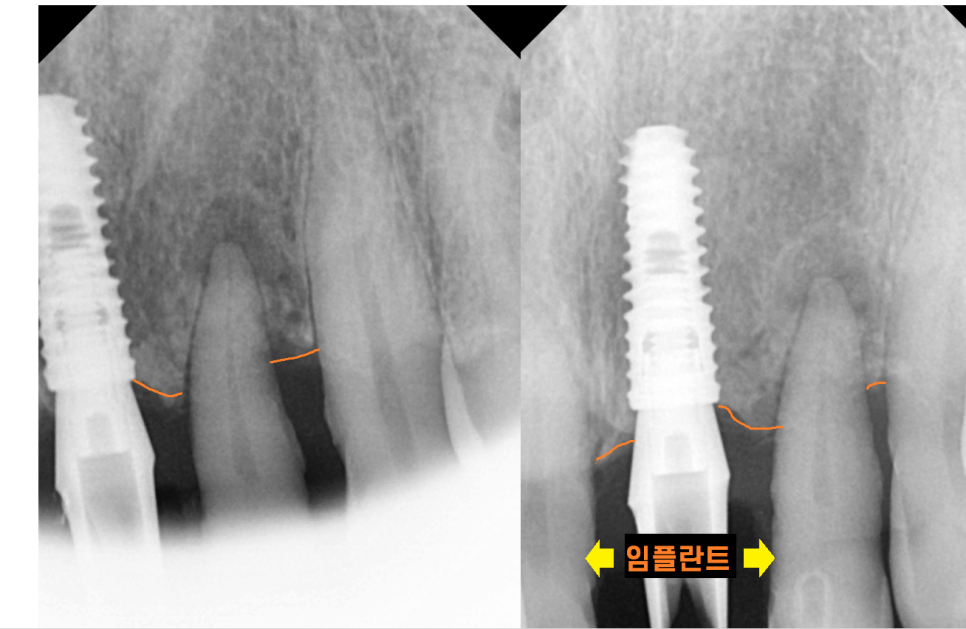

잇몸 뼈 확인을 위하여 x-ray를 찍어보니

역시나 치아를 붙잡고 있는 잇몸뼈가 없습니다.

이러니 윗니 앞니 흔들림이 발생하죠.